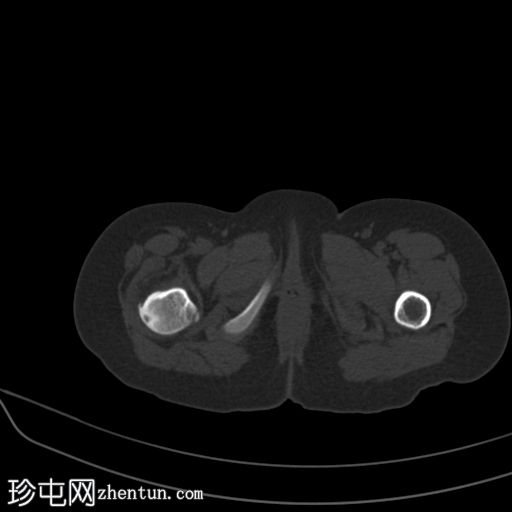

CT

在右股骨近端后外侧皮质内可见一小的透亮病灶,周围有中度硬化。内部无钙化。